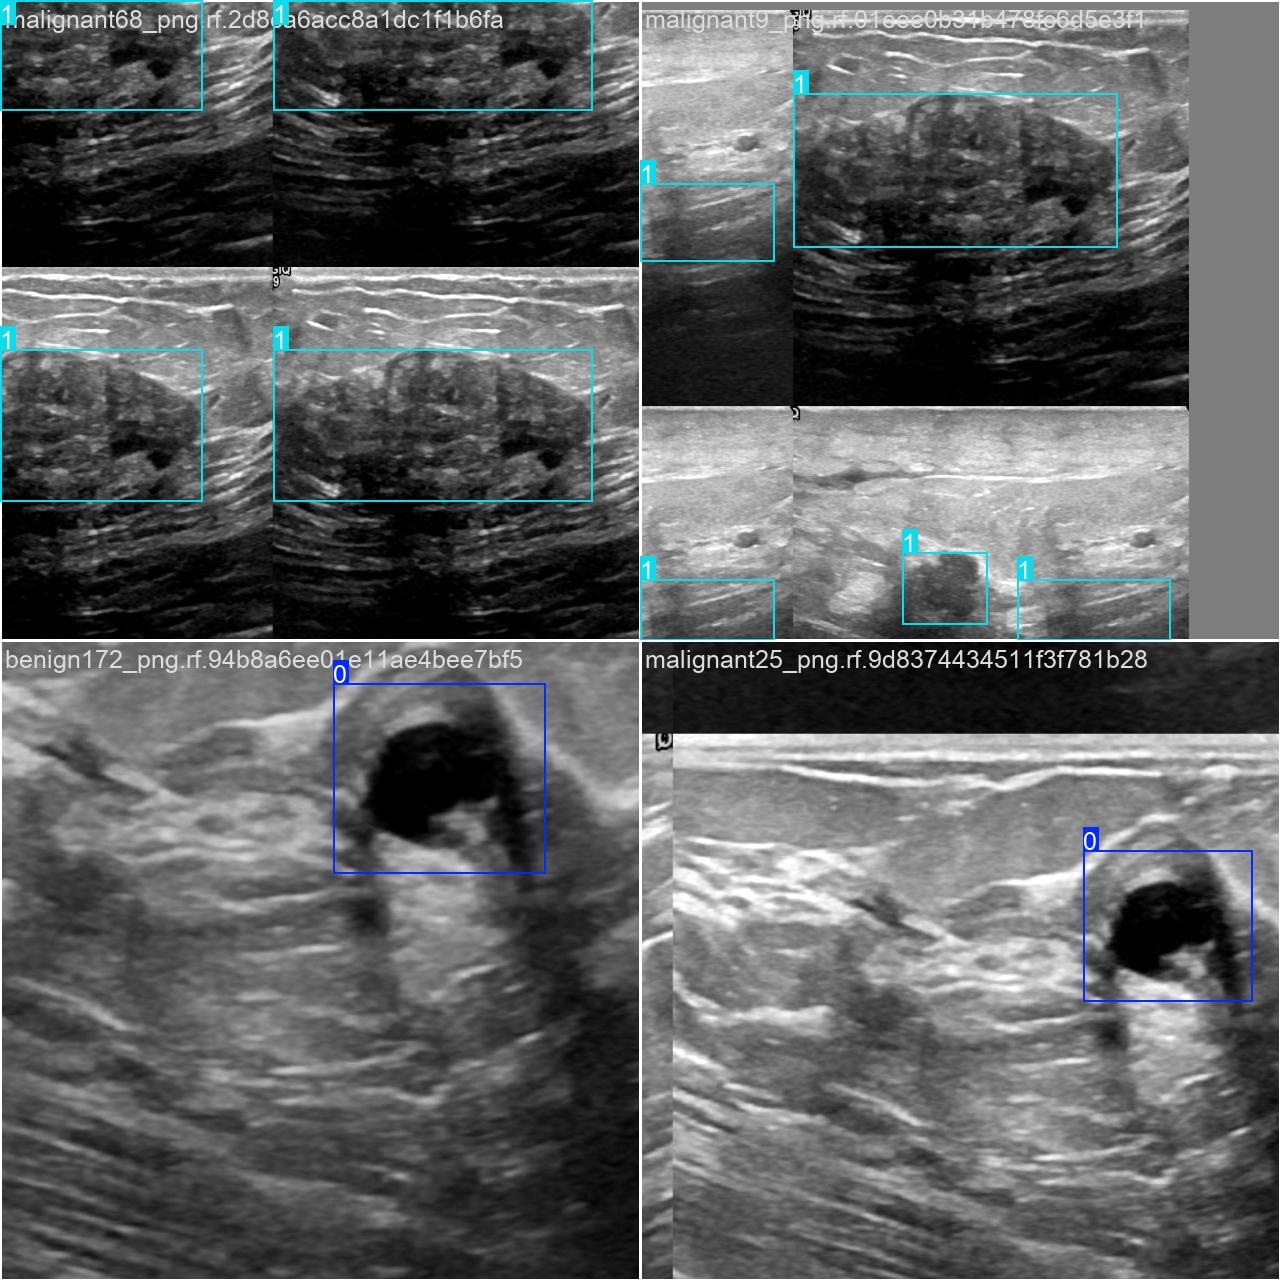

本研究使用了包含各种甲状腺结节病症相关图像的数据集,并通过Labelimg标注工具对每张图像中的目标边框(Bounding Box)及其类别进行标注。然后主要基于YOLOv8n这种模型进行模型的训练,训练完成后对模型在验证集上的表现进行全面的性能评估及对比分析。模型训练和评估流程基本一致,包括:数据集准备、模型训练、模型评估。本次标注的目标类别为甲状腺结节病症,数据集中共计包含1863张图像,其中训练集占1452张,验证集占411张。部分图像如下图所示:

部分标注如下图所示:

执行imgTest.py代码后,会将执行的结果直接标注在图片上,结果如下:

这段输出是基于YOLOv8模型对图片“imagetest.jpg”进行检测的结果,具体内容如下:

图像信息:

(1)处理的图像路径为:TestFiles/imagetest.jpg。

(2)图像尺寸为 640×640 像素。

检测结果:

(1)模型在该图片上检测到 2 个良性结节(”2 benign”)

处理速度:

(1)预处理时间:3.2 毫秒

(2)推理时间:4.1 毫秒

(3)后处理时间:45.7 毫秒

模型在处理图片时非常高效,成功检测出2个良性结节,并将结果保存到了指定目录。